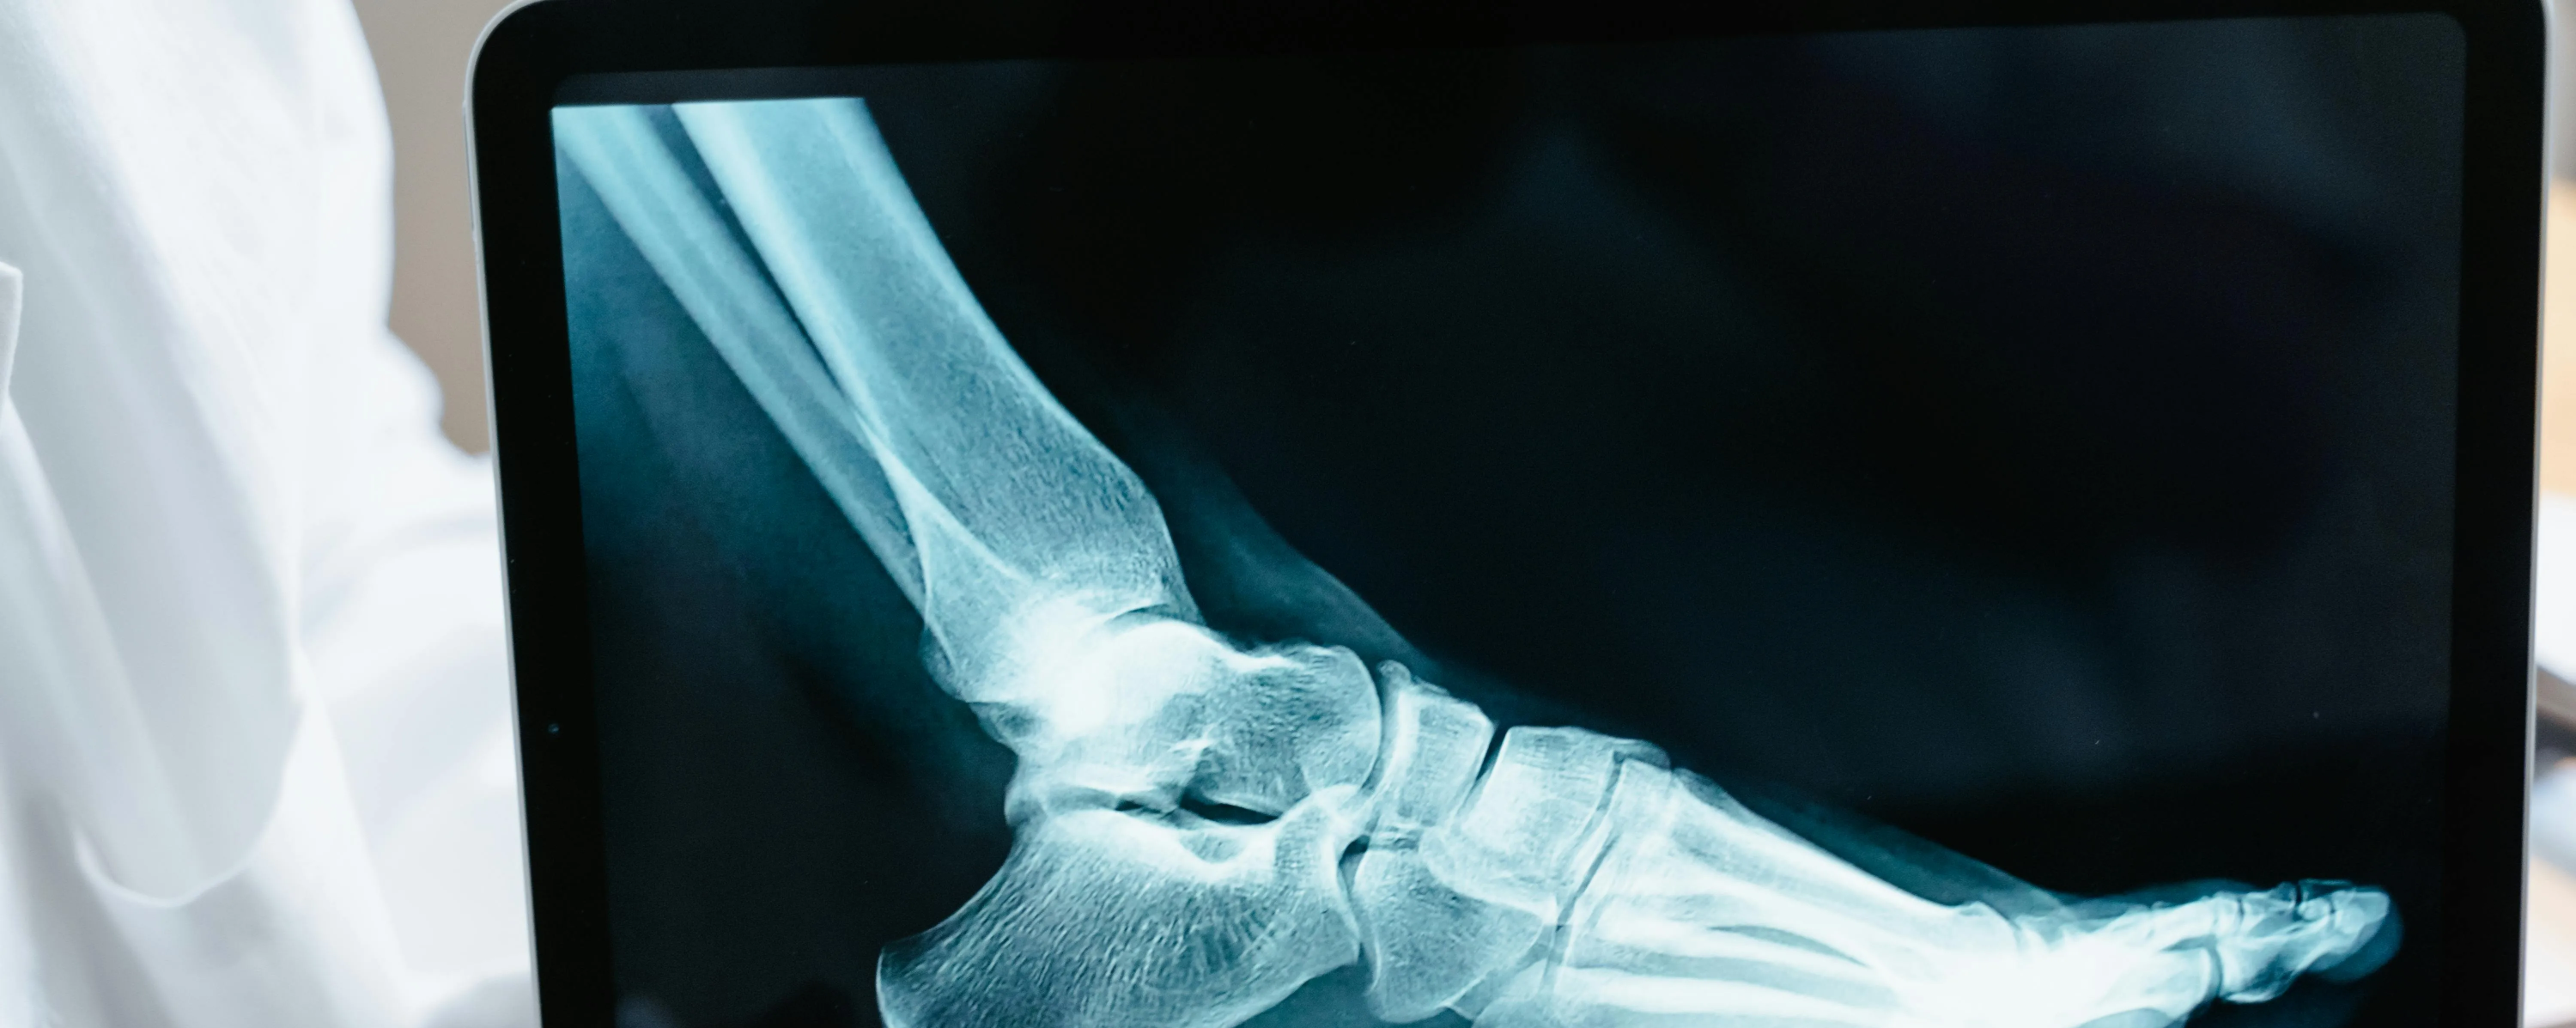

콘드로이친(Chondroitin)은 우리 몸의 연골과 결합조직 속에 자연적으로 존재하는 성분으로

관절 사이에서 충격을 흡수하고 마찰을 줄여주는 역할을 합니다.

나이가 들면서 콘드로이친이 점점 감소하면 관절이 뻣뻣해지고 통증이 생길 수 있다고 합니다.

콘드로이친 효능 2 – 연골 보호 및 재생 도움

콘드로이친은 단순히 통증을 완화하는 것에 그치지 않고,

-연골 세포의 손상을 줄이고 재생을 돕는 역할도 합니다.-

콘드로이친 효능 3 – 관절 윤활 및 유연성 개선

콘드로이친은 관절 속의 윤활 작용을 촉진해 마찰을 줄여주는 역할을 합니다.

실제로 콘드로이친은 관절액의 점도를 높여 유연성을 개선하는 효과가 있다고 합니다.